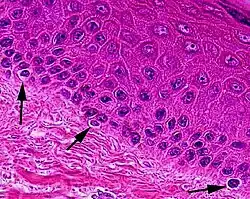

Micrograph of melanocytes in the epidermis

Typically, between 1000 and 2000 melanocytes are found per square millimeter of skin or approximately 5% to 10% of the cells in the basal layer of epidermis. Although their size can vary, melanocytes are typically 7 μm in length.